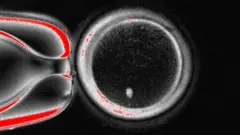

Cientistas americanos produziram, pela primeira vez, embriões humanos em estágio inicial, manipulando DNA retirado das células da pele de pessoas, fertilizadas com espermatozoides.

A técnica criada pela equipe de pesquisa da Universidade de Ciências e Saúde de Oregon, nos Estados Unidos, retira o núcleo de uma célula da pele.

Este núcleo contém uma cópia de todo o código genético necessário para a construção do corpo humano. Ele é colocado no interior de um óvulo doador, que teve suas instruções genéticas retiradas.

Eles foram fertilizados com espermatozoides e alguns deles progrediram para os estágios iniciais de desenvolvimento de embriões. Nenhum deles se desenvolveu além do estágio de seis dias.